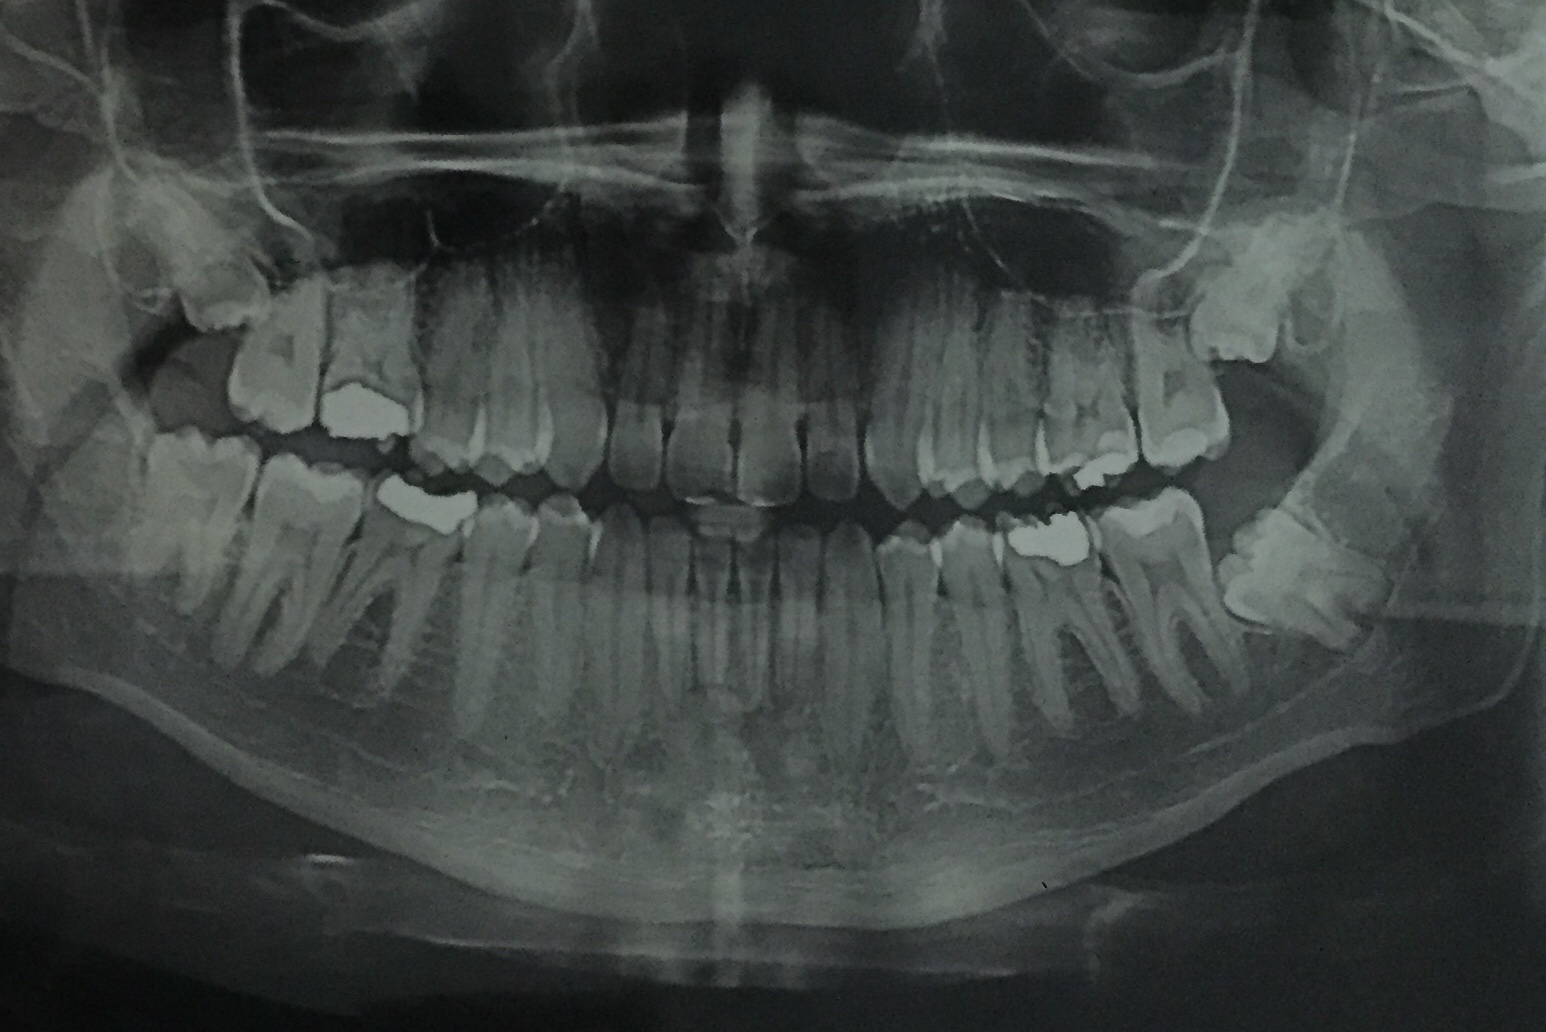

يعرف التصوير الشعاعي البانورامي أيضًا باسم الأشعة السينية البانورامية، وهو  فحص يتم  بالأشعة السينية ثنائي الأبعاد (2-D) للأسنان ،  يتم عن طريق اشعة بانوراما الاسنان التقاط   صورة واحدة كامله للفم  ، بما يشتمل تلك التصوير الأسنان للفكين العلوي والسفلي والتركيبات والأنسجة المحيطة.

الفك هيكل منحني يشابة لهيكل حدوة الحصان، بالاضافة الي ان الأشعة السينية البانورامية تنتج صورة مسطحة للبنية المنحنية وما يقدم تفاصيل عن العظام والأسنان.

اصبح الان فحص اشعة البانوراما للاسنان يتوافر في مركز الشروق ، ويتم القيام بة من خلال أطباء الأسنان و جراحي الفم، وهي أداة تشخيصية هامة لأنة يقدم المعلومات الوفيره الذي يحتاج اليها الطبيب في التشخيص تجاه الجيوب الأنفية الفكية ومكان الأسنان وتشوهات عظام الفك.